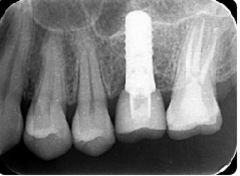

インプラントはストローマンを使用、上部構造はジルコニアセラミックス

費用は2本で総額40万円(税込44万円)(他院の相場だと税込88万円位です)